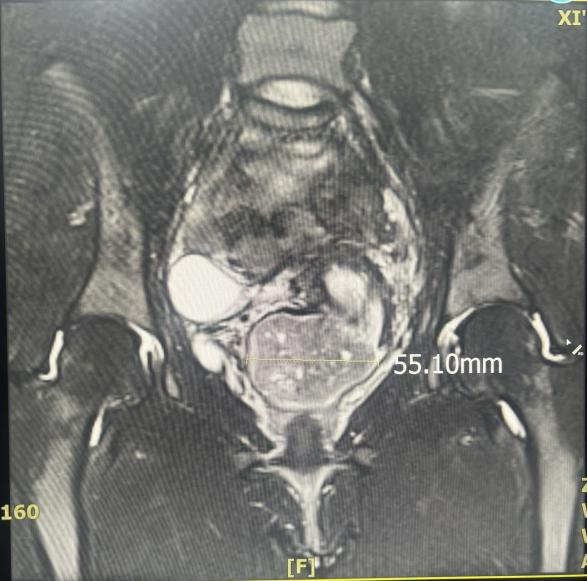

近日,西安市中医医院妇科接诊了一位患者,未婚女性,无性生活史,因“经期延长伴经量过多1年”就诊,盆腔超声提示“子宫颈平滑肌瘤(4.5×3.7cm)”,血常规提示中度贫血,盆腔核磁提示黏膜下肌瘤可能。

入院后经科室讨论,依据子宫颈黏膜下肌瘤诊疗指南:患者黏膜下肌瘤,继发月经过多致中度贫血,且有生育要求,可行宫腔镜下黏膜下肌瘤电切术,需利用镜体相对较粗的直径8.5mm电切镜才能切除宫颈肌瘤,向患者及家属告知术中可能有处女膜裂伤风险,可术中行修补术。